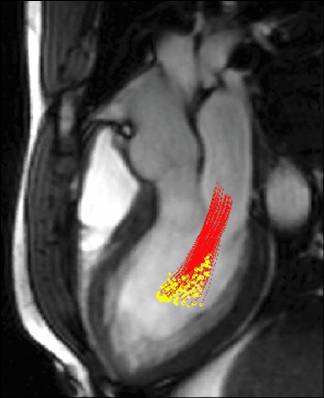

| We can study mechanical function: | Regions of motion abnormalities are readily visualized: Myocardial Infarction vs Healthy |

|

(click on the image to view animation) |